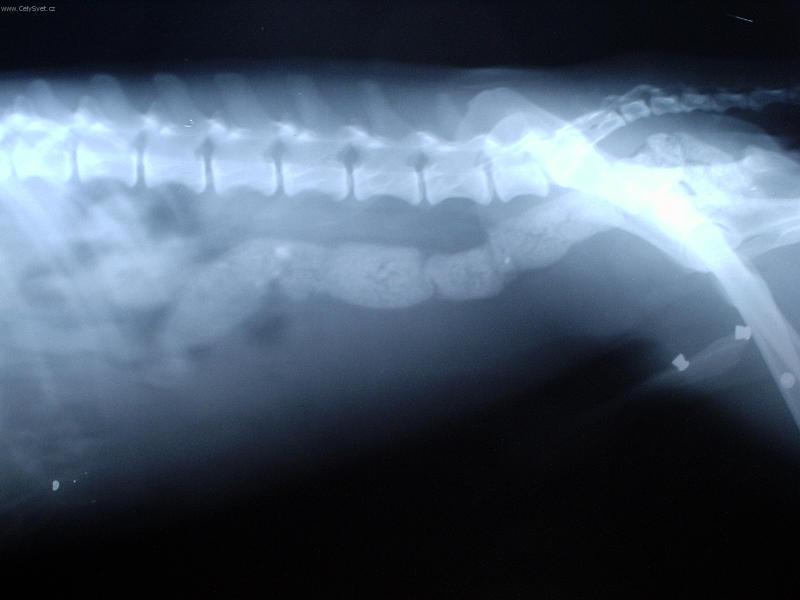

Foto galerie (fotky, obrazky): Cizí tělesa v zažívacím traktu a kostní trus.

Clanek: Cizí tělesa v zažívacím traktu a kostní trus.